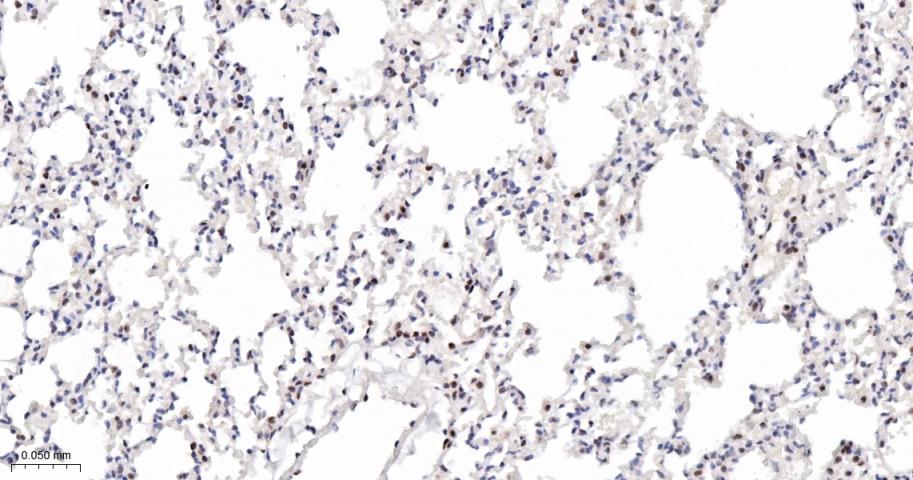

Paraformaldehyde-fixed, paraffin embedded Mouse Lung; Antigen retrieval by boiling in sodium citrate buffer (pH6.0) for 15 min; Antibody incubation with phospho-STAT3 (Ser727)  Monoclonal Antibody, Unconjugated(bsm-52210R) at 1:200 overnight at 4°C, followed by conjugation to the bs-0295G-HRP and DAB (C-0010) staining.